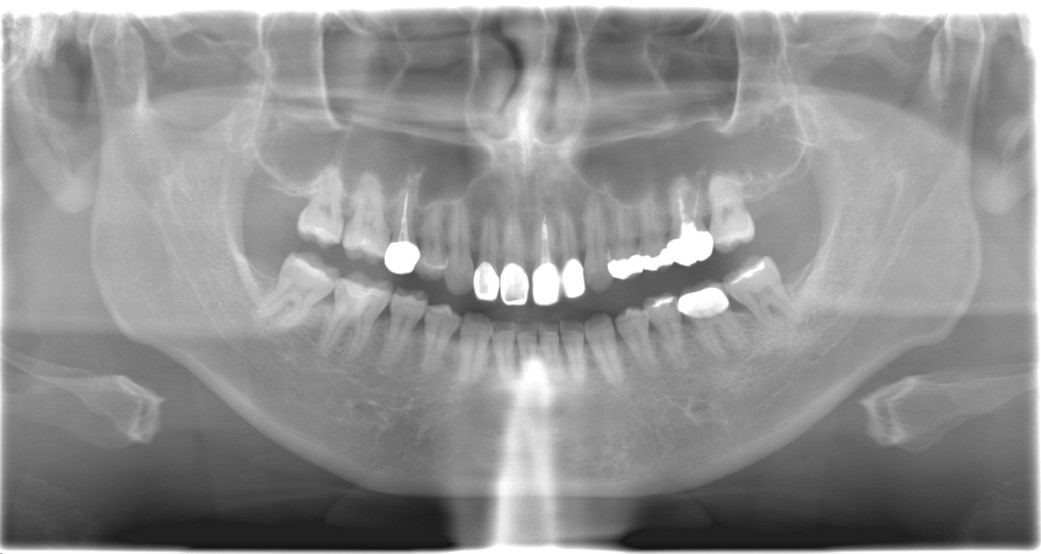

根管治療・歯内療法、感染根管治療の症例をご紹介します。2015年の初診時から2024年の現在にいたるまでの経過となります。治療から約9年後の現在も、症状や根尖病変の再発もなく良好な経過が確認できています。

診断名 | 上顎右側第二小臼歯、上顎左側第一大臼歯根尖性歯周組織炎、左右歯性上顎洞炎 |

初診時:2015年4月

初診時から8年2ヶ月経過:2023年6月

症状や、根尖病変の再発もなく、経過良好である。